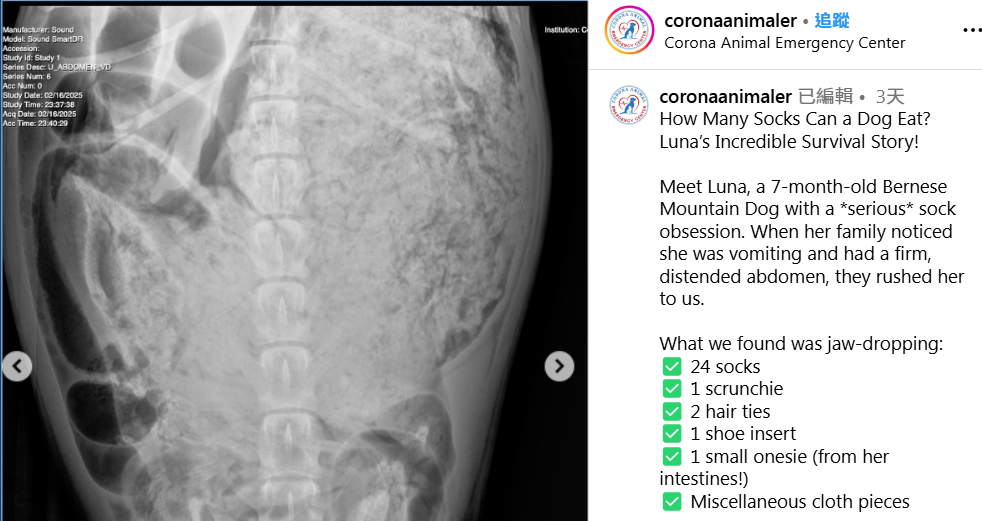

7個月大的Luna肚裡塞滿東西。(互聯網)

一隻狗的胃可裝多少襪?美國加州一隻7個月大狗狗因嘔吐被主人送往動物急症中心,X光照片顯示牠肚裡塞滿東西。醫生開刀驚見裡面滿是衣飾布料,從牠肚裡拿出24隻襪、鞋墊、布髮圈、橡根和各式各樣布碎,還有從其腸裡抽出一件嬰兒連身衣!

醫生為愛食衣物的Luna做開肚手術,清理其胃裡的襪子等異物,還有切開腸臟拿出阻塞腸道的連身衣。動物急症中心在上社交網展示從Luna肚子取出的襪子,各式各樣長短襪都有,還有牠的X光片,可見胃裡塞滿東西。Luna做手術取出肚裡異物後已恢復元氣,再次搖起尾巴。帖文提醒大家,若發現狗隻嘔吐、無力氣和肚部堅硬,應立即帶牠看醫生。